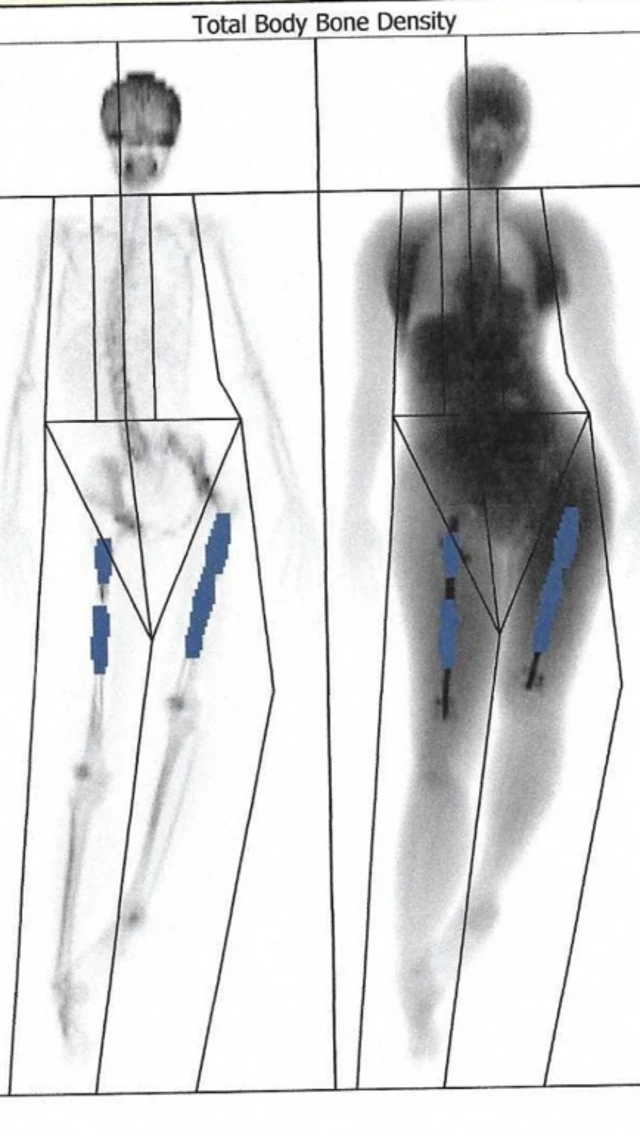

सितम्बर तक उनका दाहिना पैर सात सेंटीमीटर तक बढ़ गया. लेकिन चीजें सामान्य तरीक़े से नहीं चल रही थीं. उनके दोनों पैर छोटे-बड़े थे, जिससे उनकी रीढ़ की हड्डी टेढ़ी हो गई और उन्हें लगातार दर्द की शिकायत रहने लगी.

छह सप्ताह बाद हुए स्कैन में पता चला कि उनके दाहिने पैर में हड्डियों का बढ़ना रुक गया था. इस पैर में फीमर के दो टुकड़े रॉड से जुड़े हुए थे.